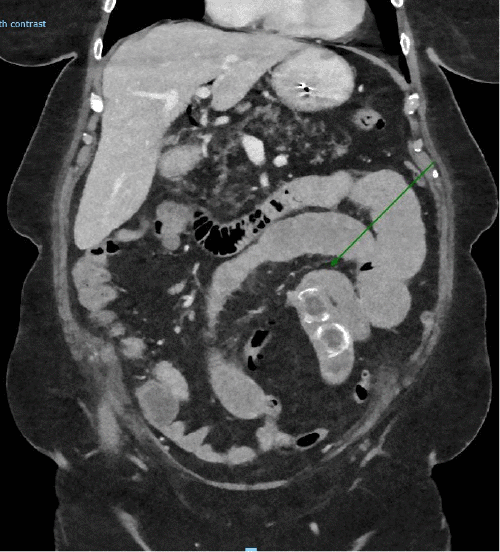

The plain abdominal radiograph demonstrated dilated loops of small bowel concerning for intestinal obstruction, and a repeat CT scan demonstrated recurrent gallstone ileus, with three calculi now obstructing the terminal ileum. Interestingly, the gallbladder was noted to be empty. (Figure 2).

Figure 2. CT Scan Demonstrating Recurrent Gallstone Ileus with Three Stones Obstructing Terminal Ileum (arrow). Published with Permission